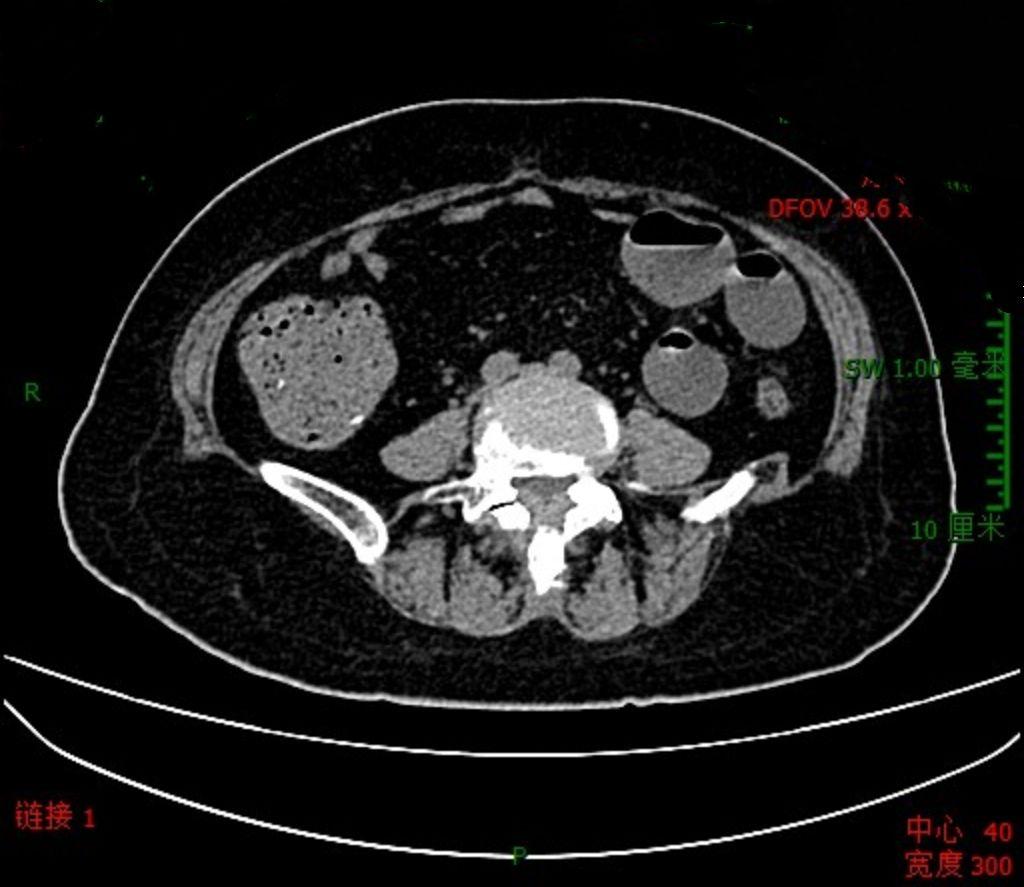

化疗后真的很容易发生肠梗阻

肿瘤化疗后,由于患者体能差,胃肠道蠕动变弱,长期卧床,确实很容易发生肠道梗阻。所以如果化疗后两三天大便不通畅,就得警惕了,早期干预,避免发生肠梗阻,或者其他更为严重的合并症。